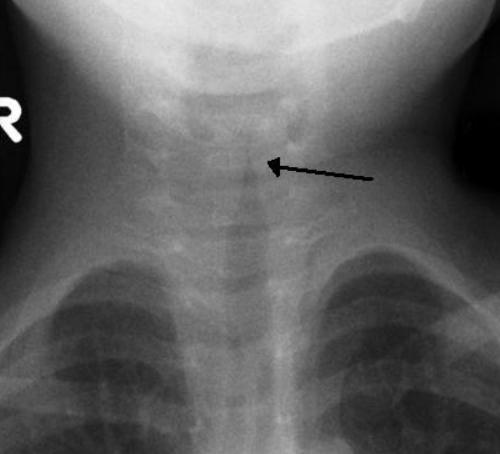

哮吼孩童是颈部X光片,可以见到声门下方气道缩窄,呈现「尖塔征象」